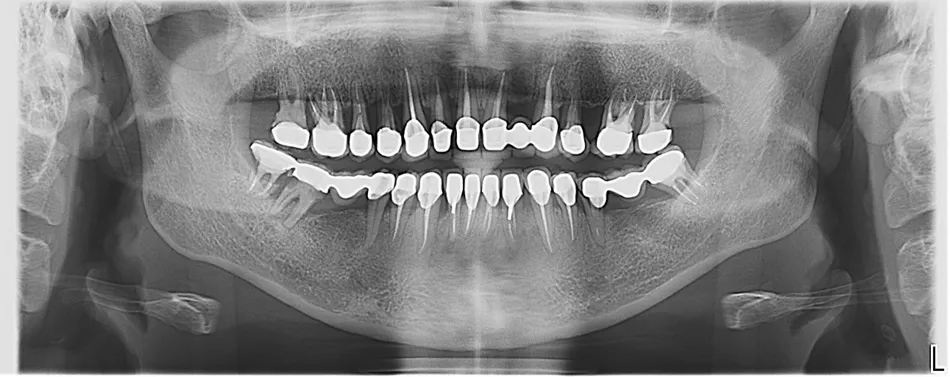

Пациентка 47 лет обратилась в клинику с жалобами на плохое состояние ранее изготовленных металлокерамических коронок и мостовидных протезов, на подвижность зубов, на кровоточивость десен, на неприятных запах из-под коронок. Также её не устраивал внешний вид и функциональность ортопедических конструкций. Но основной жалобой и проблемой для пациентки была неэффективность и длительность пародонтологического лечения, продолжающегося более 15 лет, результаты были временными, ограниченными или отсутствовали вообще. (Илл. 1–4)

В процессе сбора семейного анамнеза выяснено, что родители пациентки страдали хроническим пародонтитом. Пациентка выросла на крайнем севере России, где был ограниченный пищевой рацион (из-за труднодоступности местности) и очень плохой состав воды, в первую очередь - недостаточное содержание фтора. Еще из факторов риска – курение; нерациональное протезирование и, как следствие, неравномерное распределение жевательной нагрузки; снижение высоты прикуса; наличие большого количества поднутрений, нависающих краёв реставраций, гиперконтуров, недостаточная точность прилегания коронок; неудовлетворительная гигиена полости рта. Десны воспаленные, отечные, имелись пародонтальные карманы разной степени выраженности у всех зубов. КЛКТ выявила тяжелую степень атрофии костной ткани, дефекты костной ткани в области фуркаций, расширение пространства периодонтальной связки у множества зубов. (Илл. 5)